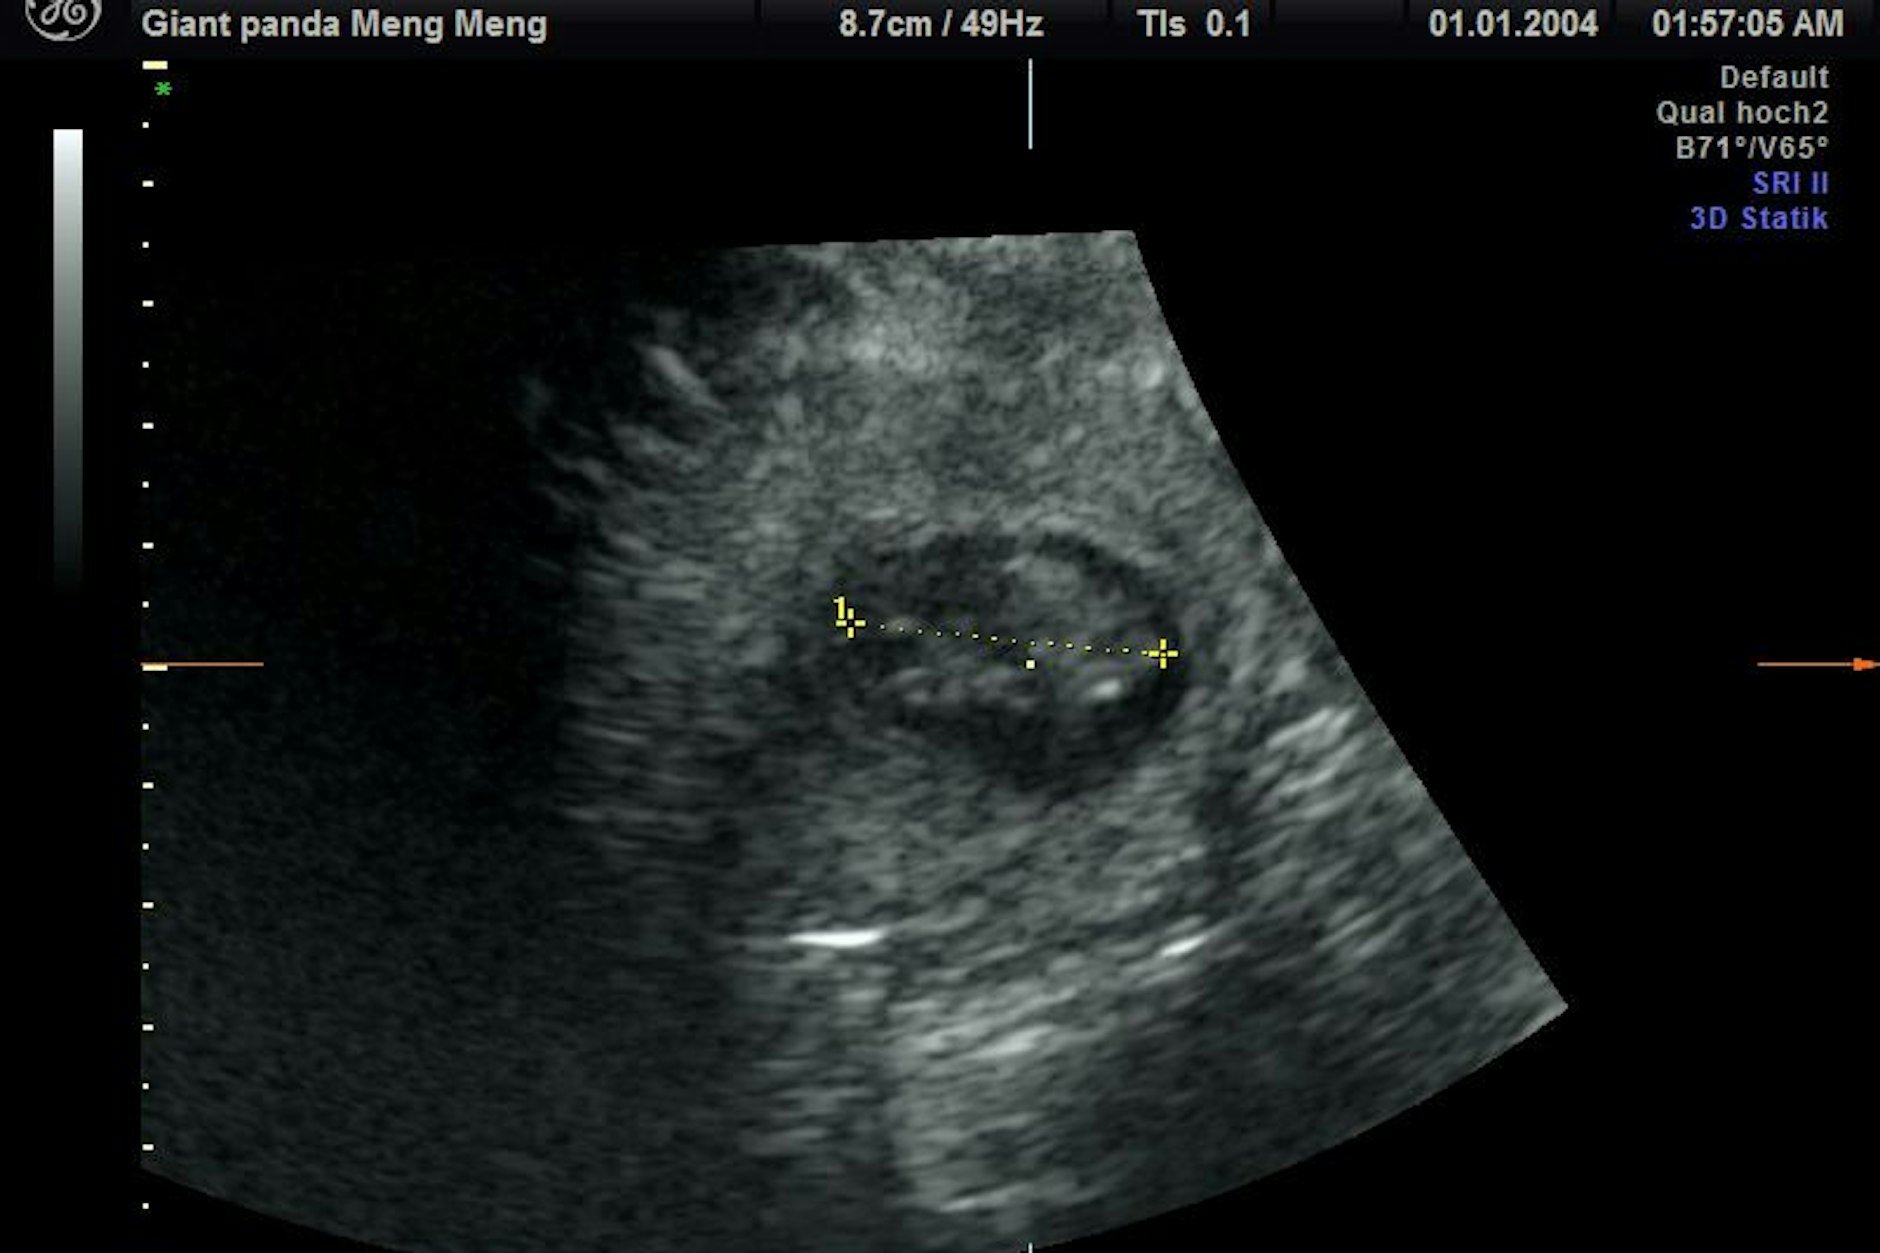

Da war wieder eine Ultraschalluntersuchung dran. Für diese hatte Meng Meng offenbar gar keine Lust mehr. Doch was dann die „Panda-Spezialeinheit“ zu sehen bekam, löste einen kleinen Jubel aus, sagte eine Zoo-Sprecherin. Erst war ein Herzschlag, dann ein zweiter auf dem Ultraschallgerät zu erkennen!

Da Hildebrandt, sein Team und die Zoo-Pfleger sich mit der Panda-Dame doch recht gut verstehen, gelang es ihnen, die China-Bärin für diese Ultraschalluntersuchung zu „überreden“, wozu das Tier nun gar keine Lust mehr hatte. „Trotz sichtlichen Bauchkneifens ließ sich Meng Meng überzeugen, in den aufrechten Stand zu kommen und das kühle Ultraschall-Gel sowie die Untersuchung mit der Ultraschall-Sonde zu akzeptieren“, sagt Hildebrandt. Das gesamte Team war zurecht stolz auf diesen bahnbrechenden Erfolg.“

Das Team wertete die Ultraschall-Bilder aus. Hildebrandt: „Die Babys sind etwa 2,5 Zentimeter groß und müssen jetzt bis zur Geburt noch ordentlich wachsen.“